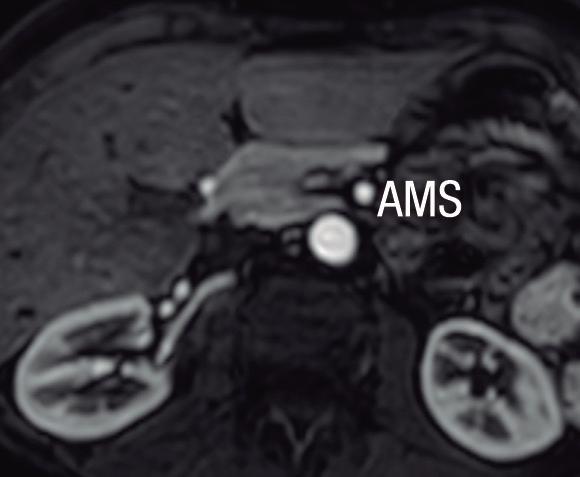

Páncreas Circumportal

El páncreas engloba a la vena mesentérica superior o vena porta, en lugar de rodear al duodeno como sucede en el páncreas anular (Figura 14). Tiene una prevalencia de hasta 2,5% según algunas series, por ende, no es tan infrecuente encontrarlo en estudios por imágenes. Se

Hipoplasia pancreática

La agenesia pancreática completa es incompatible con la vida y extremadamente infrecuente. La agenesia parcial o hipoplasia puede involucrar el brote ventral o dorsal, con mayor frecuencia este último. Puede ser una condición aislada o bien estar asociada al síndrome de heterotaxia - poliesplenia. En la hipoplasia del páncreas dorsal se observa la porción cefálica y el proceso uncinado de aspecto redondeado, con ausencia del cuello, cuerpo y cola. Suele observarse relativa prominencia

A B

postula que su origen está relacionado con una anomalía en la rotación y fusión del brote ventral con el dorsal. Es una condición asintomática, pero cobra relevancia reconocerla e informarla en pacientes que serán sometidos a cirugía del páncreas, con el fin de reducir complicaciones, particularmente la fístula pancreática.25, 26

del proceso uncinado, que se prolonga por detrás de los vasos mesentéricos (Figura 15). Es imprescindible efectuar el diagnóstico diferencial y descartar exhaustivamente una lesión neoplásica que provoque atrofia del páncreas corpocaudal, distal al tumor. Los individuos con agenesia del páncreas dorsal suelen ser asintomáticos, aunque se ha descripto un riesgo incrementado de padecer diabetes debido a que el mayor porcentaje de los islotes de células de Langerhans se hallan en el páncreas distal. 27

parcial del brote dorsal)

A) Resonancia magnética, secuencia T2, plano coronal. Se observa un páncreas “truncado”, con ausencia de tejido glandular a la izquierda del cuello (flecha), coincidente con una agenesia parcial del brote embriológico dorsal. La cabeza de flecha nos muestra a la porción cefálica prominente, redondeada. B) Resonancia magnética, secuencia T1 con contraste, plano axial. Flecha: Limite de finalización de la glándula, a la izquierda de la arteria mesentérica superior. Cabeza de flecha: Porción cefálica prominente, redondeada. C) Resonancia magnética, secuencia T1 con contraste, plano axial, corte más caudal. Las flechas muestran hipertrofia relativa del proceso uncinado (brote ventral), el cual llega a ubicarse por detrás de los vasos mesentéricos superiores, incluso superando el plano de la arteria. AMS: arteria mesentérica superior.

A) Resonancia magnética, secuencia T1 sin contraste, plano axial. Tejido pancreático con típica señal hiperintensa en secuencia de ponderación tisular T1 (cabezas de flecha), rodeando a la vena porta (VP). B) Resonancia magnética, secuencia T1 con contraste, fase portal, plano axial. VP: vena porta, VE: vena esplénica, AMS: arteria mesentérica superior.